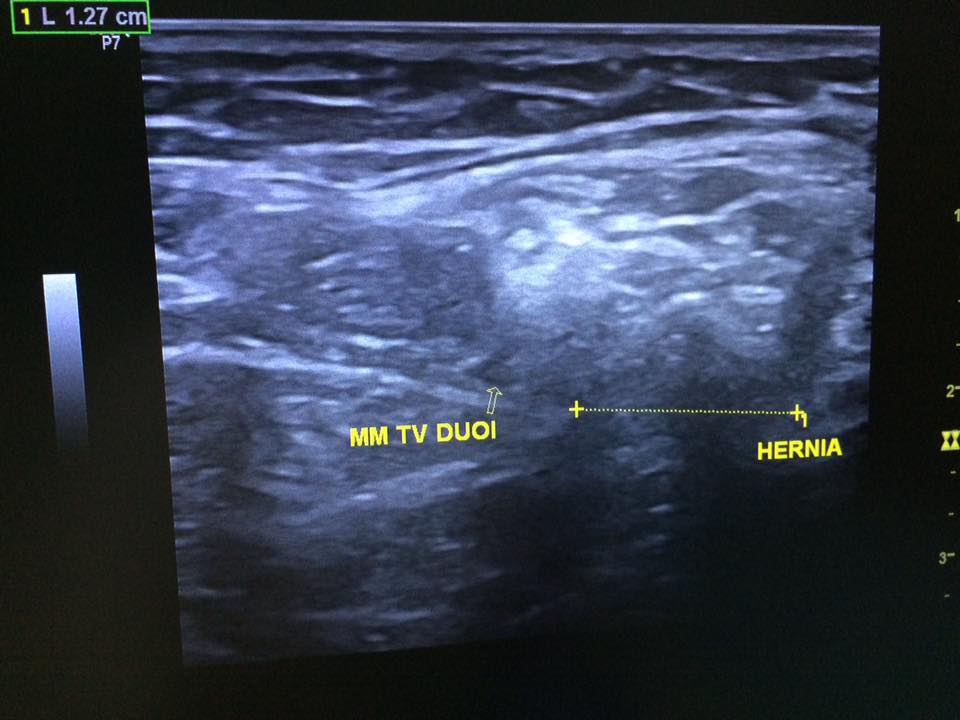

Staff member 4. Nam 67t Ls: chuẩn bị mổ thoát vị ben t => bs pt muốn sa lại trước pt Clip sa bẹn trái Chẩn đoán? 14908238_565556773642431_7094452599200745576_n.jpg 14900543_565556830309092_6731208493409609365_n.jpg 14963305_565556790309096_4643616292348455768_n.jpg 14908193_565556873642421_859291706916583555_n.jpg 14900519_565556826975759_1726480362463028455_n.jpg Nguồn: Code: https://www.facebook.com/groups/cdhaOnline/permalink/780379048767244/ Spoiler: Đáp án: Thoát vị, chưa thấy bc nghẹt... Vị trí: cổ túi thoát vị phía NGOÀI BÓ MẠCH THƯỢNG VỊ DƯỚI VÀ PHÍA TRÊN DC BẸN=> tv gián tiếp (tv giá tiếp còn 1 dh ko quan trọng là túi tv nằm dọc phía nông và ngoài so với bó mạch thừng tinh- như case này) Quan trọng và khó khăn là cắt ra dc bẹn và mm tv dưới -------------------------------------- Video này được chia sẻ với mục đích nâng cao hiểu biết và kinh nghiệm cho cộng đồng những người làm y khoa. Không vì mục đích vụ lợi nào khác. Những mô tả và kết luận bệnh lý trong video này mang tính chất tham khảo và chỉ dành cho những người có chuyên môn. Vui lòng kiểm tra thật kỹ thông tin trước khi áp dụng vào thực tế. Nếu bạn là chủ nhân video và cảm thấy không hài lòng về điều này, hãy liên hệ với chúng tôi: [email protected] You must log in or register to reply here. Share: Facebook Twitter Reddit Pinterest Tumblr WhatsApp Email Share Link